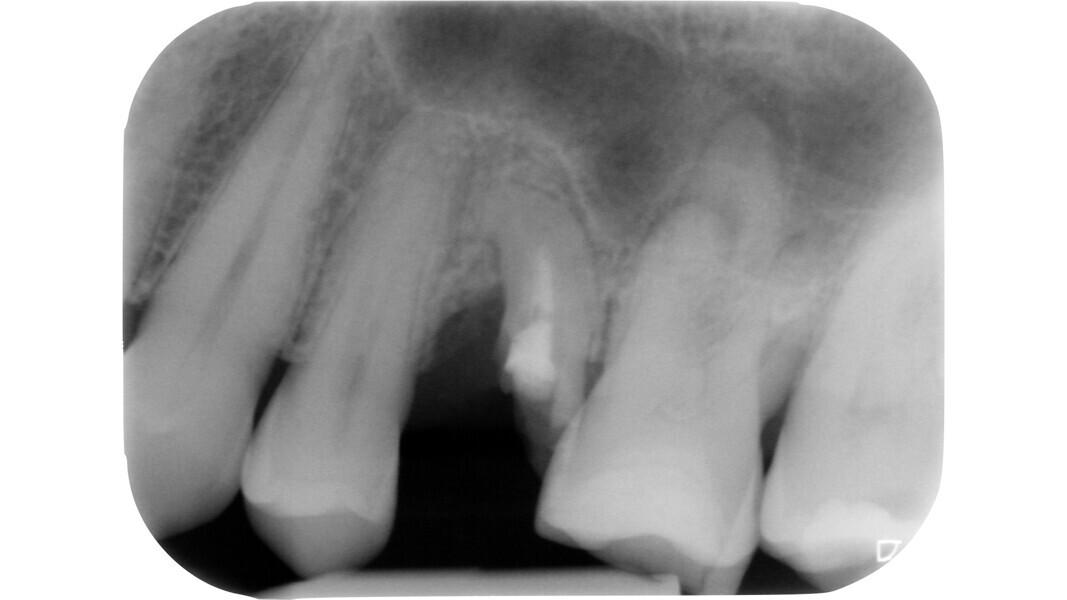

Fig. 15: Pre-op radiograph of a mandibular molar affected by irreversible pulpitis.

Fig. 16: Intermediate phase of treatment, after pre-endodontic reconstruction, access cavity preparation and preliminary canal shaping. Note the presence of a pulp stone on the floor of the chamber with a translucent appearance.

Fig. 20: Post-op radiograph.